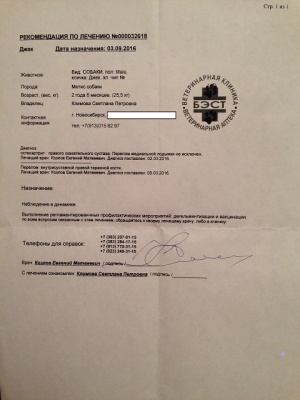

– предоплата за проведение компьютерной томографии правого скакательного сустава (КТ) врач Горшков Сергей Сергеевич, и операции (снятие пластины) хирург Козлов Евгений Матвеевич, клиника Бэст (чек 1, заключение КТ – документ 1, лист назначений – документ 1-1) – 5000 руб.;

– окончательная оплата за проведение компьютерной томографии правого скакательного сустава (КТ) врач Горшков Сергей Сергеевич, и операции (снятие пластины) хирург Козлов Евгений Матвеевич, клиника Бэст (чек 3, товарный чек 3, лист назначений – документ 3) – 7756 руб.;

– предоплата за проведение компьютерной томографии правого скакательного сустава (КТ) врач Горшков Сергей Сергеевич, и операции (снятие пластины) хирург Козлов Евгений Матвеевич, клиника Бэст (чек 1, заключение КТ – документ 1, лист назначений – документ 1-1) – 5000 руб.;

– окончательная оплата за проведение компьютерной томографии правого скакательного сустава (КТ) врач Горшков Сергей Сергеевич, и операции (снятие пластины) хирург Козлов Евгений Матвеевич, клиника Бэст (чек 3, товарный чек 3, лист назначений – документ 3) – 7756 руб.;

Лист приема и назначений от 15.06.2016, итоговый чек за период 02.03.2016 - 07.06.2016.